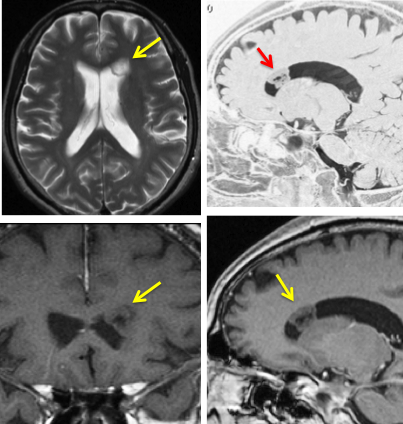

片側性水頭症

左尾状核から発生したものです。モンロー孔を閉塞して,片側性水頭症となっています。腫瘍がトリュフみたいにゴツゴツしているのも特徴です。

下のガドリニウム増強T1では,部分的に増強されます。

もちろん無症状ですが,年齢が若かったので全摘出しました。